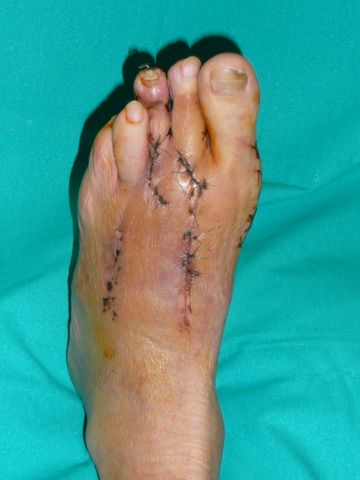

Hallux valgus intervenidos